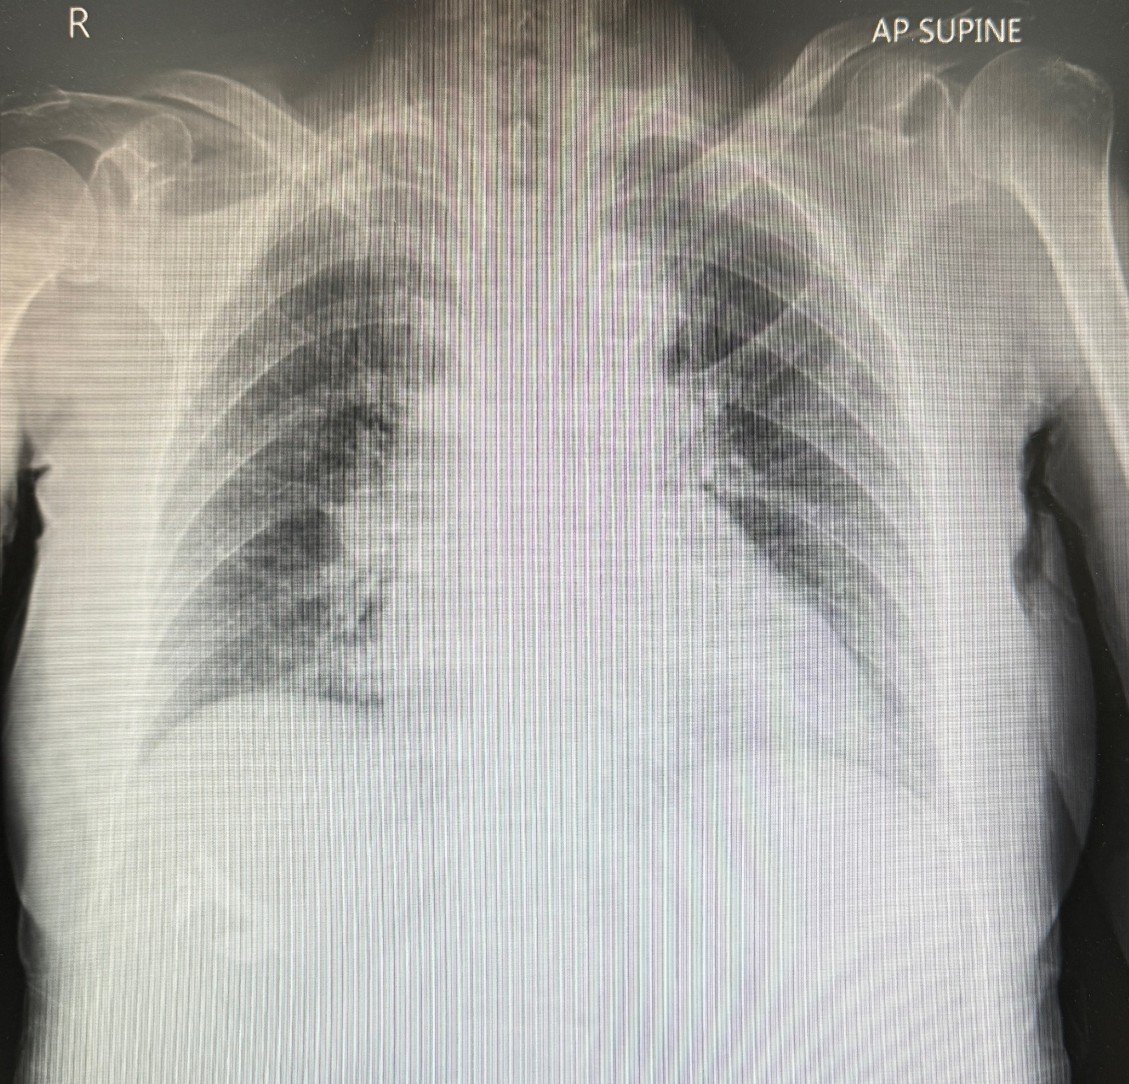

Relevant Clinical History and Physical Exam

A Thai 97-year-old woman, who's totally independent, documented history of AF with severe TR S/P T-TEER for 4 years ago, HTN, DLP, mild dementia. She presented with a 12-month history of unspecified exertional dyspnea, NYHA III. Physical examination revealed stable hemodynamics, well-orientation with sign of chronic heart failure and LVH. Appearing peripheral abnormalities on palpation and murmur on auscultation, which's compatible with severe tricuspid regurgitation and severe aortic stenosis.

Relevant Test Results Prior to Catheterization

Her ECG revealed AF without pre-existing BBB. Transthoracic echocardiography revealed concentric LVH with 65% of LVEF, severe biatrials enlargement, normal RV function , multiple heart valve abnormalities indicated to a TriClip device with severe TR, moderate functional MR and severe calcific aortic stenosis. As the Heart Team discussion, several cause of symptoms was suspected. We brain stormed to design her individual appropriated-solution, on concerning of natural history in each disease.